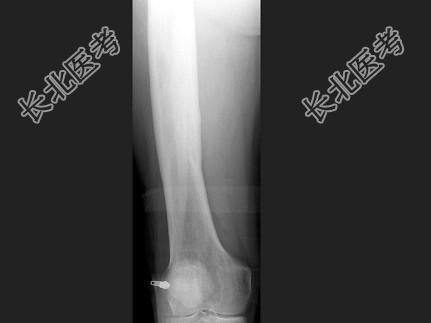

单项选择题男,67岁, 右侧股骨痛,结合图像, 最可能的诊断是 ( )

A、骨纤维结构不良

B、维生素D缺乏病

C、成骨不全

D、软骨发育不全

E、畸形性骨炎